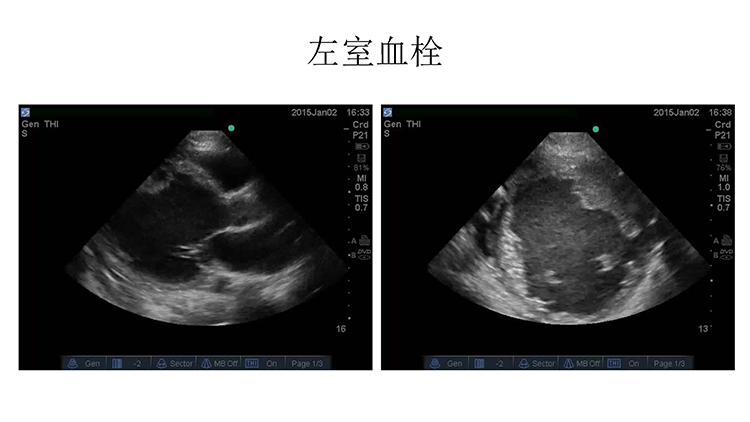

心脏外科术后VA-ECMO辅助1例汇报